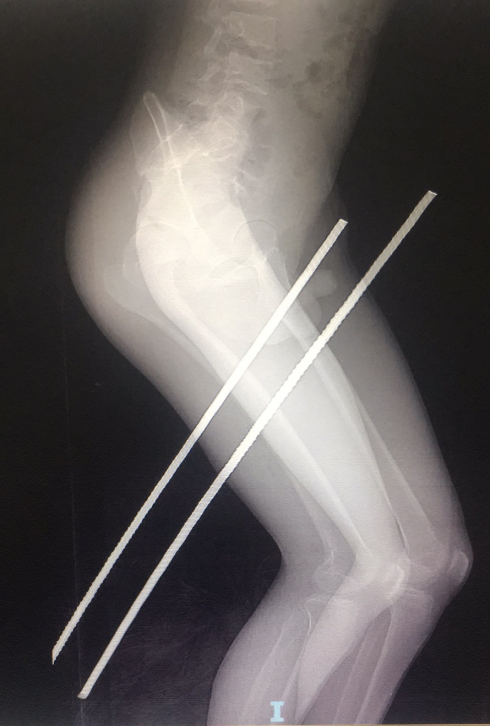

伤者影像检查图

经院方检查,有两根钢筋分别贯穿男子双腿,其中一根从大腿往上贯穿,差点插入大动脉。该院手显微血管外科紧急会诊后,开通绿色通道,在核酸结果未出的情况下,穿着防护服进行紧急手术。手术历经1个多小时,钢筋顺利从男子大腿取出,目前已脱离危险。

疫情防控期间,为了所有病患的安全,所有手术前都必须进行核酸检测。虽然经过系列检查显示,钢筋正好从小张大腿的坐骨神经及股动、静脉之间穿过,暂未对血管造成损伤,但对小张的神经产生了损伤。而且钢筋多留在小张腿内一分钟,就多一份风险。